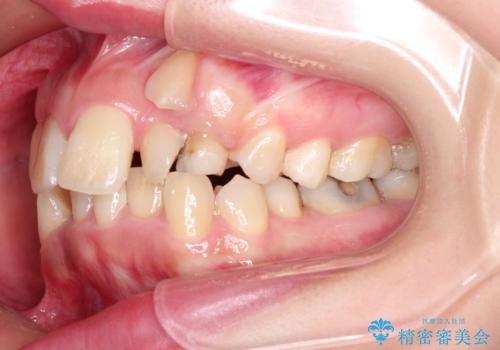

犬歯が変な位置にある 抜歯矯正により正しい位置へ

左上の犬歯が通常の位置より、かなり上方にあり、乳歯の残存と前歯のがたつきがありました。

残った乳歯と上下左右の永久歯を1本ずつ抜歯して、ワイヤーにて矯正することとしました。